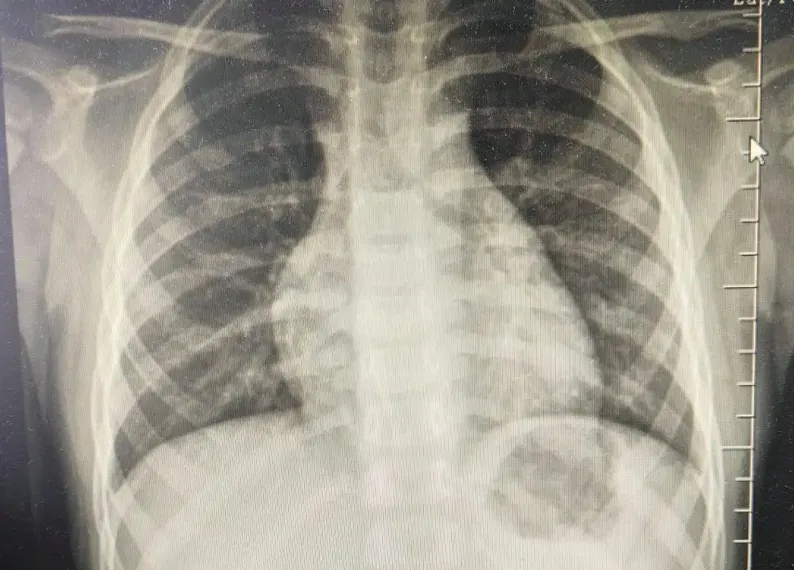

若出现以上症状应及时就医,完善检查:如血常规、C反应蛋白、肺部CT、胸部CT检查等相关检查,排除肺炎的可能。